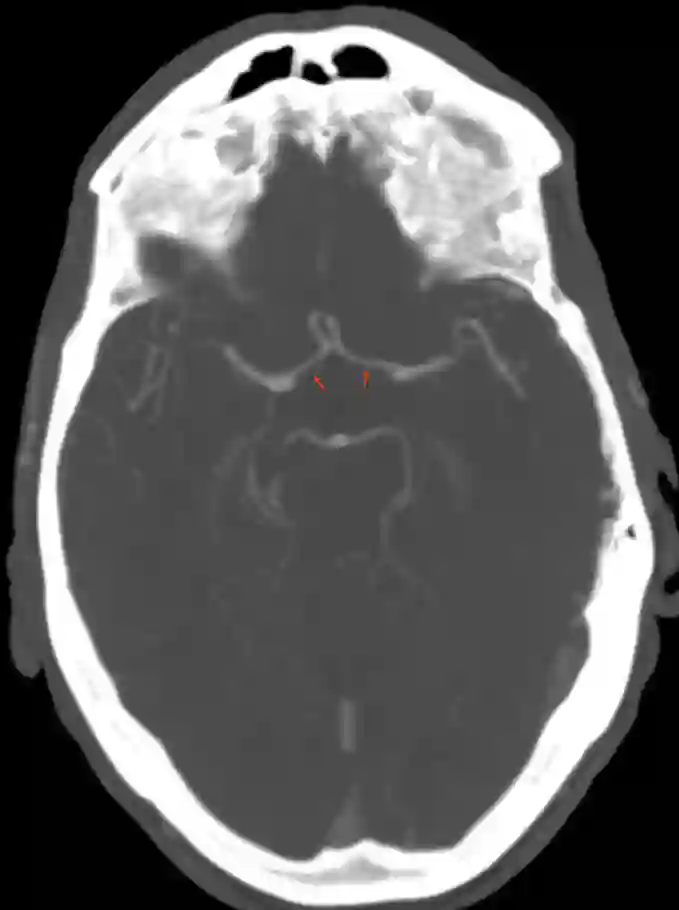

Arteria cerebri anterior in der CT Angiographie

CT Angiographie der Arteria cerebri anterior (A1 Segment, roter Pfeil)